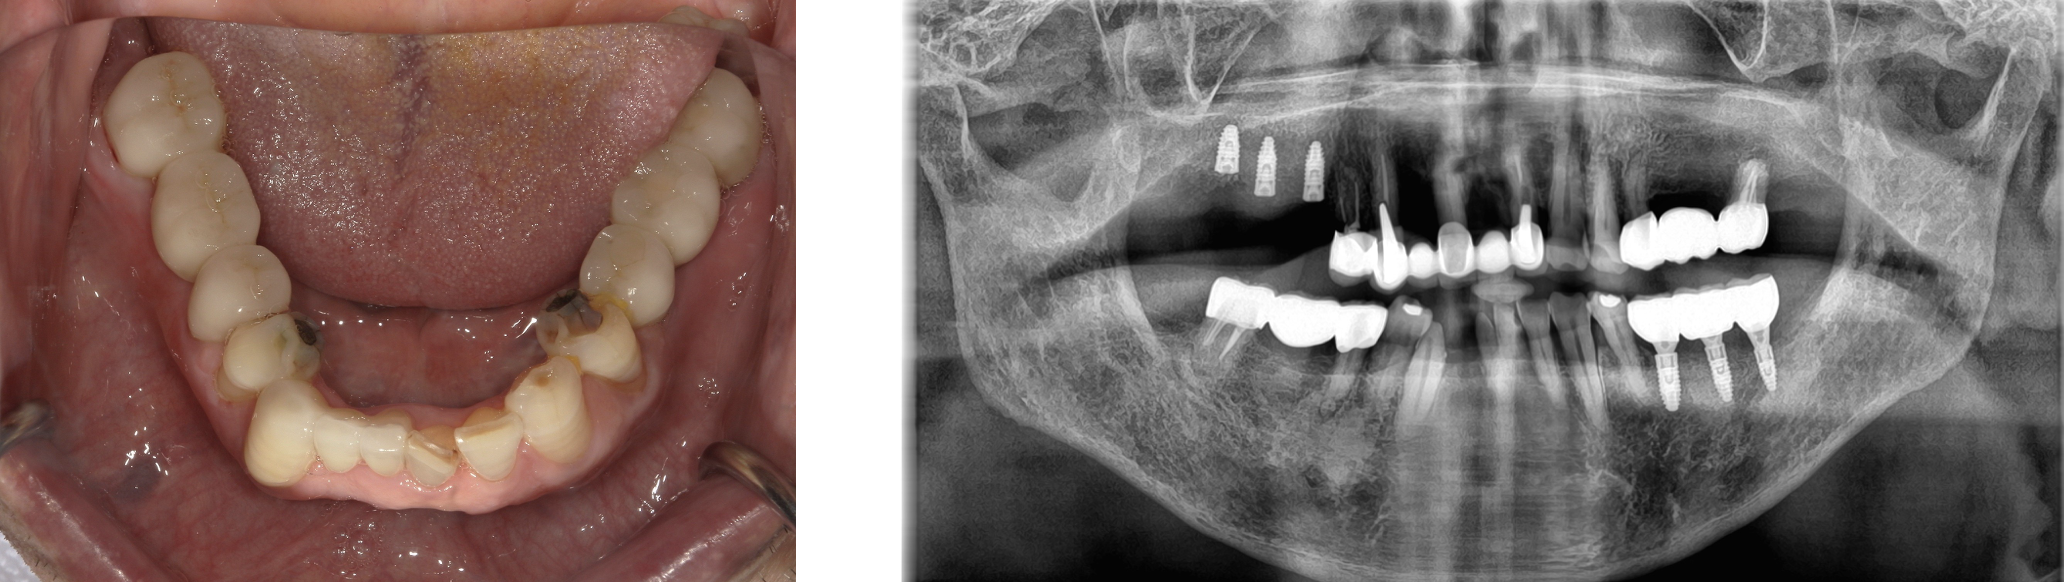

インプラント 症例3

左下567番 右上567番にインプラントを行った症例

入れ歯、ブリッジから変更